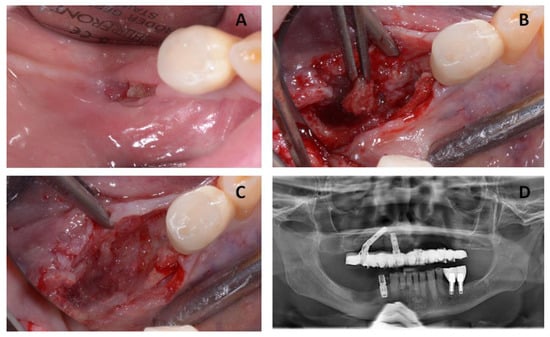

After total healing was achieved with no complications and no further signs of relapse of the MRONJ lesion, two zygomatic implants were inserted in May 2017. The zygomatic implants used in this study were Zygomatic Noris ® (Noris Medical Ltd., Nesher, Israel) with sizes of 45 mm (REF: NM-F4445) and 35 mm (REF: NM-F4435) in length and 3.5/4.2 mm in diameter, with 45° angled multi-unit abutments (Figure 4).

Figure 4. (A,B) Intra-operative images of the patient showing the steps of two zygomatic implant preparations on the posterior left side of the maxillary bone. (C) Insertion of two zygomatic implants. (D) Intra-operative image showing the mucoperiosteal flap being repositioned and sutured.